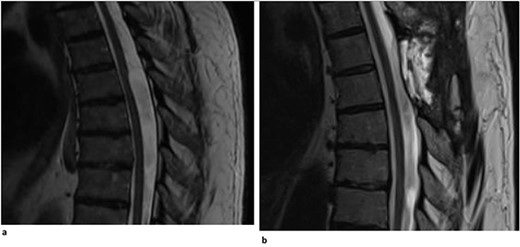

A 40-year-old woman presented with a 3-year history of progressively worsening interscapular pain radiating around the rib cage on the right, difficulty with ambulation, and right foot numbness. Physical examination demonstrated myelopathic symptoms, with 3+ reflexes in both lower extremities, clonus, and Babinski, as well as difficult tandem gait. Thoracic MRI showed an arachnoid web at the T5-T6 vertebral levels (Fig. 2a). The patient underwent a T5-T6 laminectomy with intradural exploration. A large arachnoid web was encountered and resected using microsurgical tools and technique. Postoperatively, the patient reported improvement in her pain and ambulation. Follow-up MR imaging demonstrated resolution of the dorsal indentation and cord expansion (Fig. 2b).

(a) Dorsal indentation demonstrated in thoracic spine preoperatively (Patient B). (b) Postlaminectomy and resection of posterior arachnoid web demonstrating resolution of dorsal indentation and cord signal changes (Patient B).